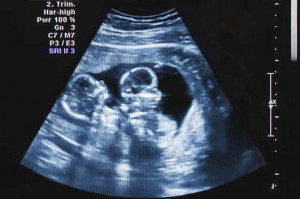

C’est au début de la grossesse, à la première échographie que vous apprenez la gémellité. Vous allez tout de suite comprendre qu’une grossesse gémellaire nécessite une surveillance nettement plus stricte que pour une grossesse simple. En effet, celle-ci augmente les risques de diabète gestationnel, d’hypertension, d’œdème, de protéines dans les urines et ainsi de pré-éclampsie. Afin prendre toutes les précautions nécessaires, vous serez amenée à faire deux fois plus d’échographies que pour une grossesse classique. Si vos bébés ont chacun un placenta (grossesse bichoriale), une échographie par mois sera programmée pour surveiller leur croissance et leur morphologie. Elle vous permettra aussi de prévenir d’éventuelles malformations ou encore d’un risque d’accouchement prématuré. Et si vos bébés partagent le même placenta (grossesse monochriale), une échographie sera mise en place tous les 15 jours dès la seizième semaine d’aménorrhée. Elles permettent de vérifier que vos bébés grandissent correctement et qu’ils ne se mettent pas en déséquilibre. Enfin, lors des dernières semaines, des consultations hebdomadaires avec votre médecin sont préconisées. De cette manière, il pourra répondre à vos dernières préoccupations et veiller sur votre état de santé et celui de votre petit bout jusqu’à la fin.